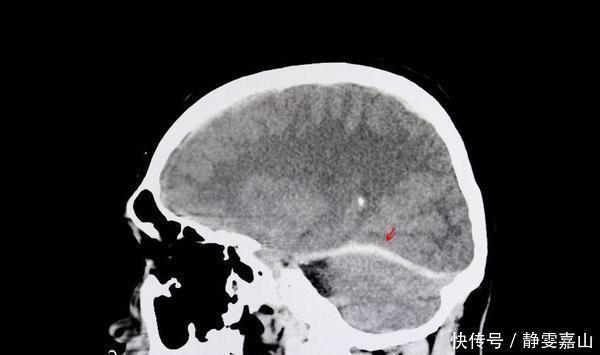

老年痴呆症是一种脑部疾病,很多人单纯的以为只是记忆力衰退而已,其实不然,老年痴呆症是一种由于脑部萎缩导致的一系列记忆、行为、语言、以及认知方面都会出现问题的脑部疾病。随着近年来对这种病症的研究更加的深入,了解也更多。